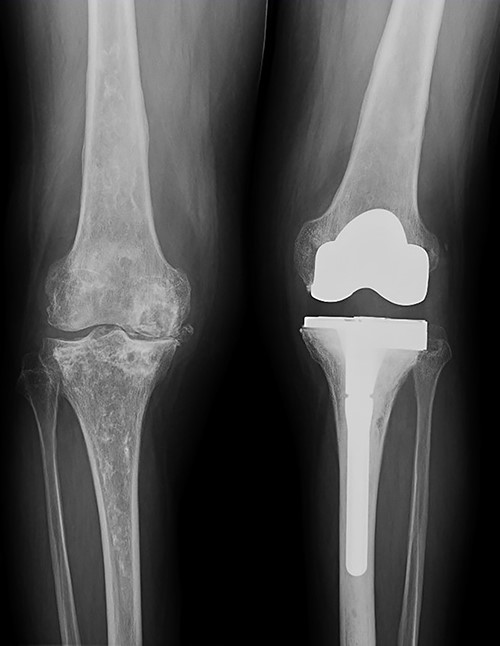

In the subsequent follow-up, pain progressively increased in the contralateral knee. Standing X-rays confirmed a severe deterioration of the right knee (Fig. 7). Given the bone defect and the consequent instability (Fig. 8), a CCK-type prosthesis was required, including medial femoral condyle blocks. The microbiological results were again negative, whereas the pathology results confirmed both severe osteoporosis and osteonecrosis.

Evolution of the right knee by standing radiographs during follow-up with progression toward joint space disappearance (Kellgren–Lawrence 4) in a severe varus deformity.